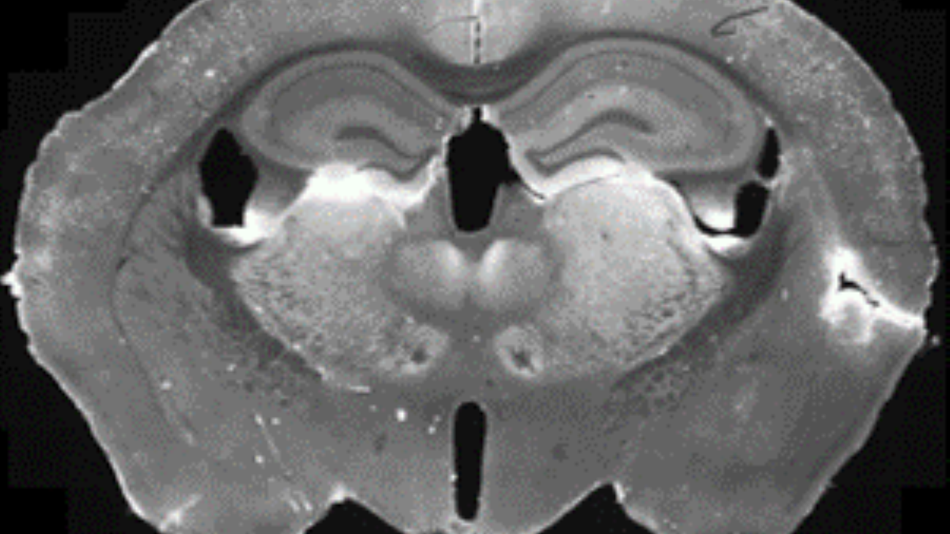

Woher wissen Wissenschaftler, wo und wie viele Zellen sich in den einzelnen Regionen des Gehirns befinden?- Kartierung der Gehirnzellen

© MedUni Wien / Neuronale Zellbiologie

MitmachstationVom Hirnschnitt zur fluoreszierenden ZelleThema: Gesundheit NaturwissenschaftenMachen Sie praktische Erfahrungen mit echtem Hirngewebe und entdecken Sie, wie Neuronen zum Leuchten gebracht werden.Medizinische Forschungsmeile17:00 - 23:00 -